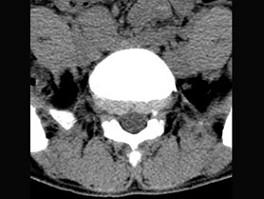

问题 男,29岁,腰痛伴下肢轻度麻木,有外伤史,请结合所提供图像,选择最佳答案 ( )

选项 A、S向后滑脱 B、未见异常 C、L向后滑脱 D、S向前滑脱 E、L向前滑脱

答案 E